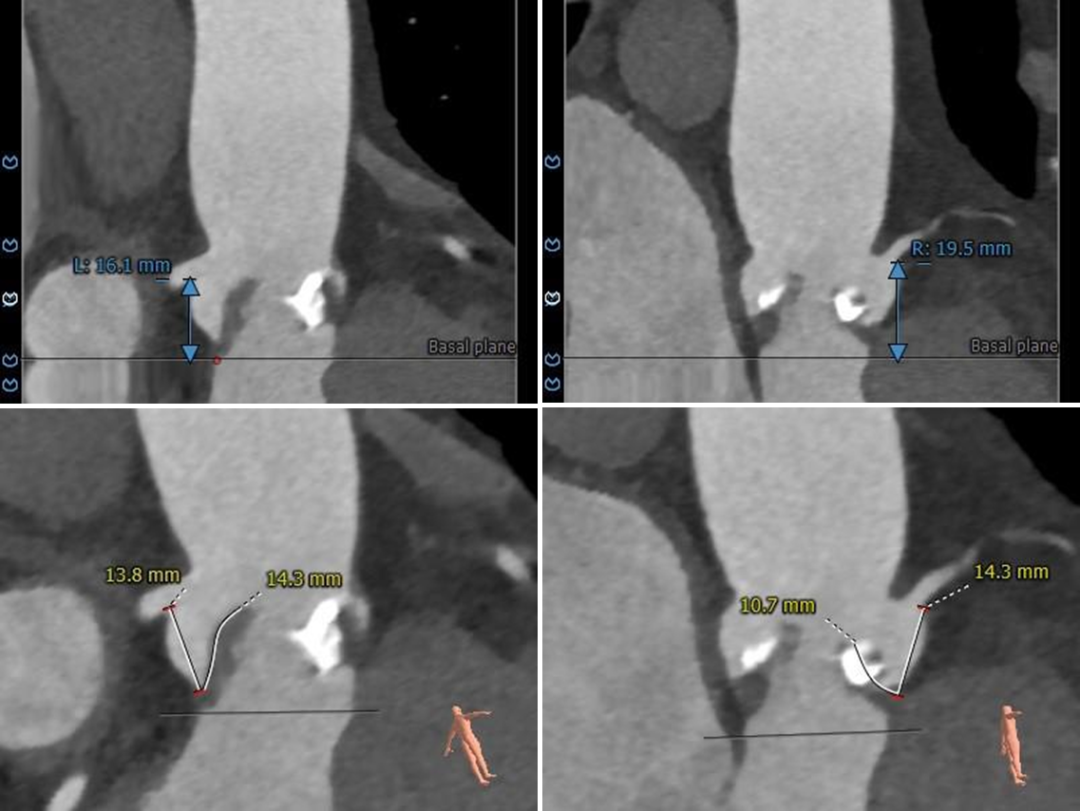

冠脉测量

冠脉开口高度可,切线角度测量,

左窦瓣叶长于LCA开口到瓣叶根部距离

连续时相观察左窦瓣叶动度灵活,

收缩期瓣叶接近左冠开口高度;

3D打印模型22mm球囊扩张测试,左窦冗余空间小

病例特点

功能性二叶瓣,R-N间团块状钙化融合,CT测量及3D模型体外球扩测试提示左冠阻挡风险高,术中需结合预扩表现可积极采取冠脉保护,必要时采取“烟囱支架”策略。

• 功能性二叶瓣,R-N之间团块状钙化融合,瓣叶增厚,团块钙化挤压支架,存在瓣周漏及瓣膜移位风险;

• 左窦瓣叶略长,动度灵活,存在左冠阻挡风险;